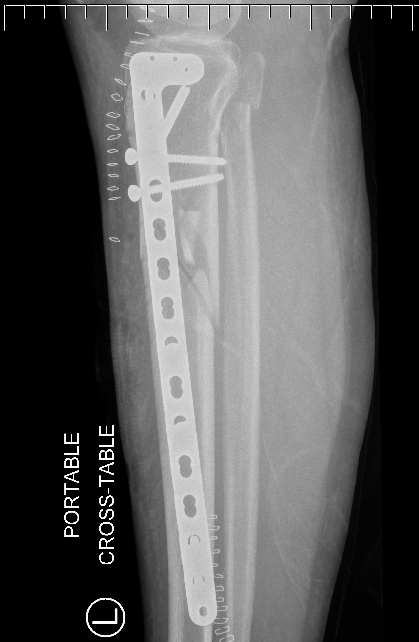

Plate Proximal Tibia Fractures

Nail + Plate fixation

Indications

Elderly

Allow early weight bearing

Technique